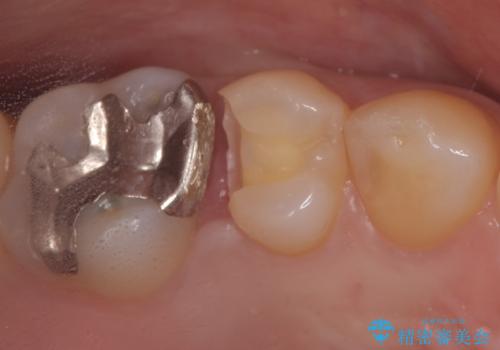

セラミックインレー 虫歯の治療

- 定期健診で虫歯が見つかり、治療が必要となりました。材料の物性を説明し、セラミックインレーでの治療となりました。

接着操作時にはラバーダム防湿を行いました。